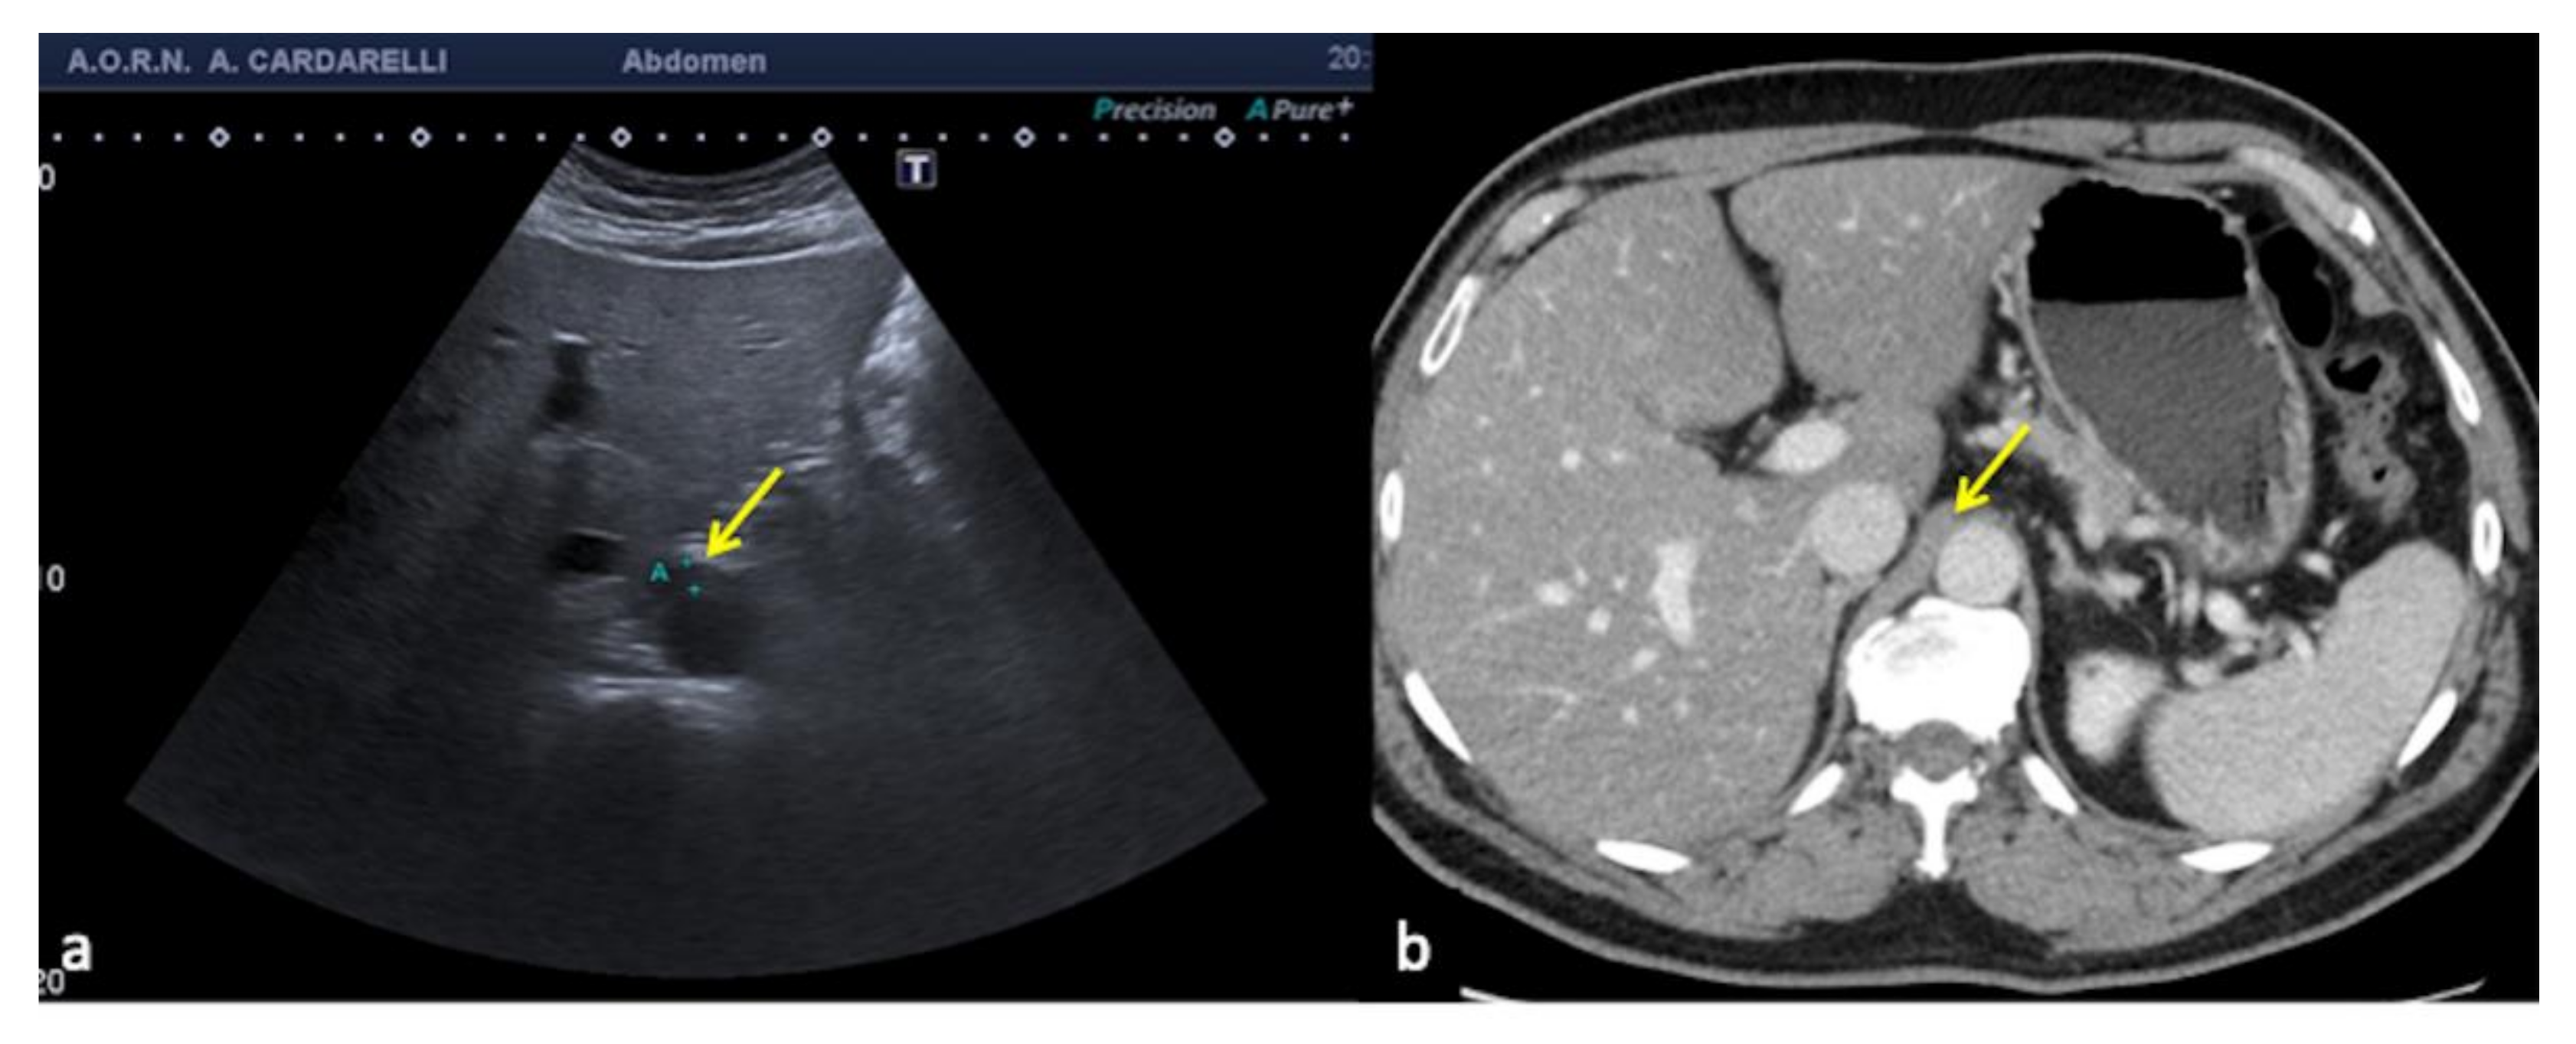

3.1.1. The Side Lobe Artifact